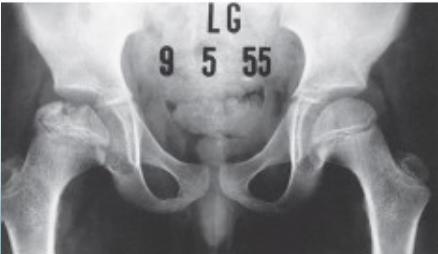

Radiographic Stages:

-

Initial/ Bone Death Stage - May initially appear normal on x-ray

- Increased density followed by collapse

Revascularization and Repair Stage - Reduced density and fragmentation on x-ray

Distortion and Remodeling Stage - Distortion, flattening (coxa plana)

- Enlargement (coxa magna) with partial uncoverage

Radiological Progression:

Progression: Sclerosis → Collapse → Fragmentation → Remodeling

Imaging Examples: